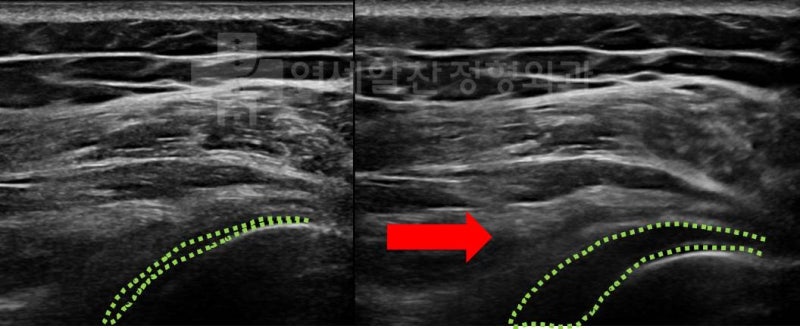

골절이 유합된 상태로 외상(골절)후 장기간 고정에 의한 유착성 관절낭염 진단하에 관절수액팽창술(hydro-dilatation) 및 재활치료를 권고하였다.

어깨의 가동범위 확보를 위해서는 물론 어깨 관절 자체의 문제만 해결해도 좋아지는 경우들이 많다. 하지만 흉추의 문제 또는 경추의 문제로 인한 기능부전이 동반되었을 경우 치료가 잘 되지 않는 경우들이 있다. 이 환자의 경우도 전체적인 사진에서 관찰해 보면